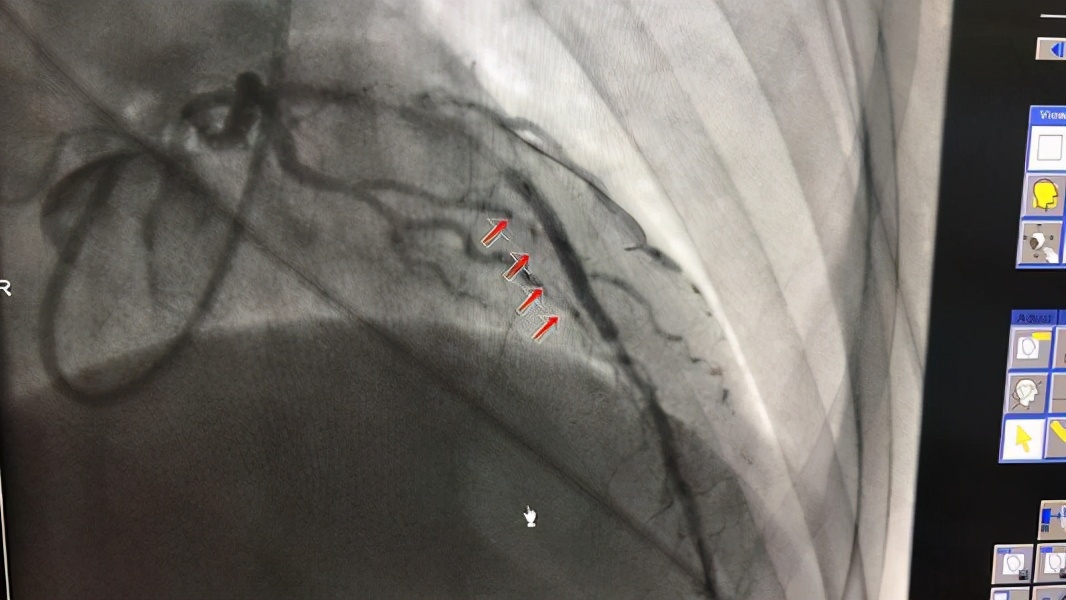

多导联心电图是诊断的主要依据。ECG特征如下

异常的 p波不能识别,心房或交界。有的无 P波,有的有逆行 P波。一般情况下,心室率在160-250/分钟之间,无法用脉搏或心脏听诊来测量。R-R间期均匀而规则。该 QRS波群与正常窦性 QRS波群形态相同,间隔小于0.10秒。T的改变提示心肌缺血